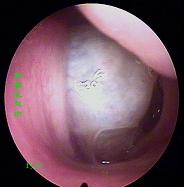

鼻炎长期得不到有效治疗导致鼻息肉以及鼻腔囊肿

经常鼻塞、流脓鼻涕、头痛多为鼻窦炎、鼻息肉等。除了流鼻涕外,长期伴有头疼症状。是早晨疼还是夜间疼?怎么减轻症状?在线咨询为你解答。